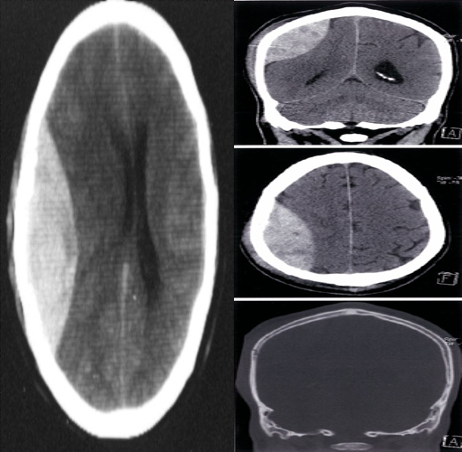

Cranial vault fracture with epidural hematoma CT head (without IV contrast; top: brain window, coronal plane; middle: brain window, axial plane; bottom: bone window, axial plane)

An epidural hematoma (EDH) is visible as a biconvex, heterogeneous, hyperdense extra-axial collection in the right hemicranium. Mass effect on the adjacent cerebral parenchyma and right lateral ventricle has produced contralateral midline shift . The hematoma does not cross the coronal or the lambdoid suture. A scalp hematoma is present, and a fracture of the underlying right parietal bone is visible on the bone window image.